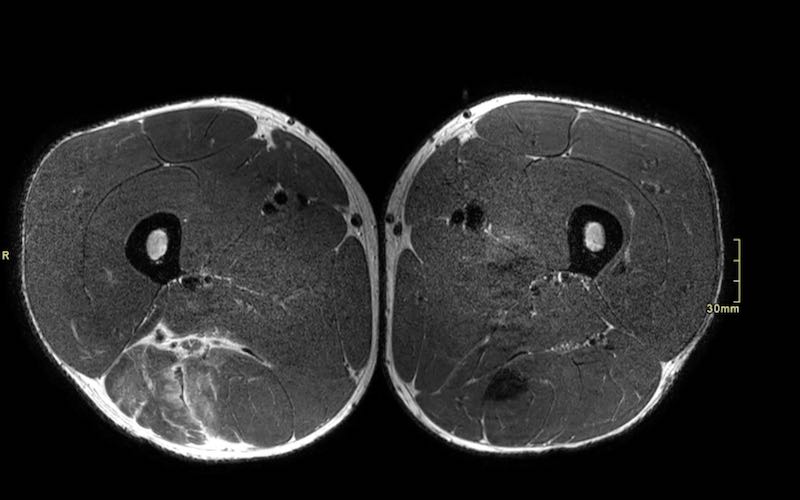

Mặt phẳng coronal so với mặt phẳng axial

Chỉ dựa vào các hình ảnh coronal đơn thuần, đôi khi khó có thể phân loại chính xác mức độ biến dạng. Cần sử dụng các hình ảnh axial để quan sát kỹ hơn.

Trên các hình ảnh axial này, có thể thấy tăng tín hiệu và dày lên của gân cơ nhị đầu đùi bên trái (vòng tròn chấm vàng) khi so sánh với bên không bị tổn thương (vòng tròn chấm trắng).

Toàn bộ phức hợp cơ hamstring của cả hai chân cần được khảo sát trên tất cả các chuỗi xung để so sánh bên tổn thương với bên hamstring lành.